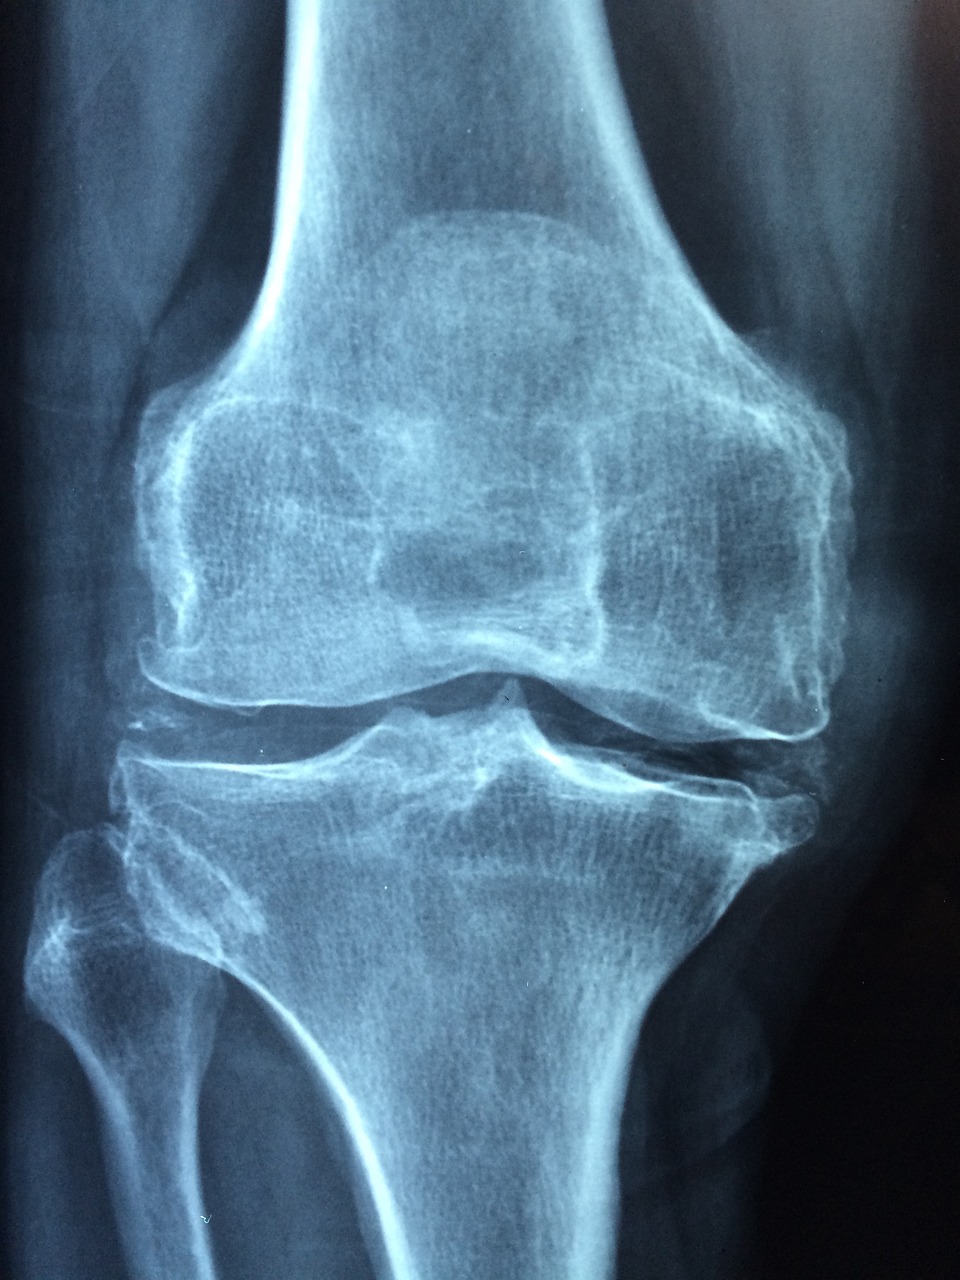

골관절염

골관절염은 나이가 들면서 연골이 닳아 없어지는 질환으로, 무릎 통증의 가장 흔한 원인 중 하나입니다. 연골이 닳아 없어지면 뼈가 직접 맞닿아 마찰을 일으켜 통증이 발생하며, 이로 인해 무릎의 움직임이 제한될 수 있습니다.